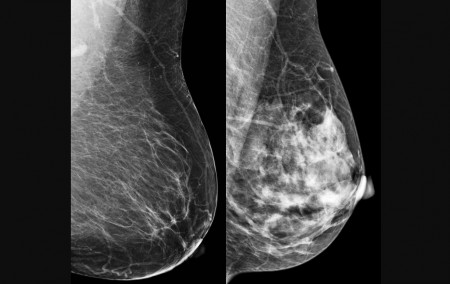

El cáncer de mama es la principal causa de muerte por tumor en la población femenina (imagen: CDC)

El Instituto Nacional del Cáncer (Inca) señala que el cáncer de mama es uno de los tipos más frecuentes entre las mujeres en Brasil (excluyendo el cáncer de piel no melanoma) y la principal causa de muerte por tumor en la población femenina. Para el año 2025 se estimaron 73.000 nuevos casos, siendo el Sudeste la región con mayor incidencia, según la publicación Control del cáncer de mama en Brasil: datos y cifras 2025, lanzada para conmemorar Octubre Rosa, el mes de concienciación y lucha contra la enfermedad.